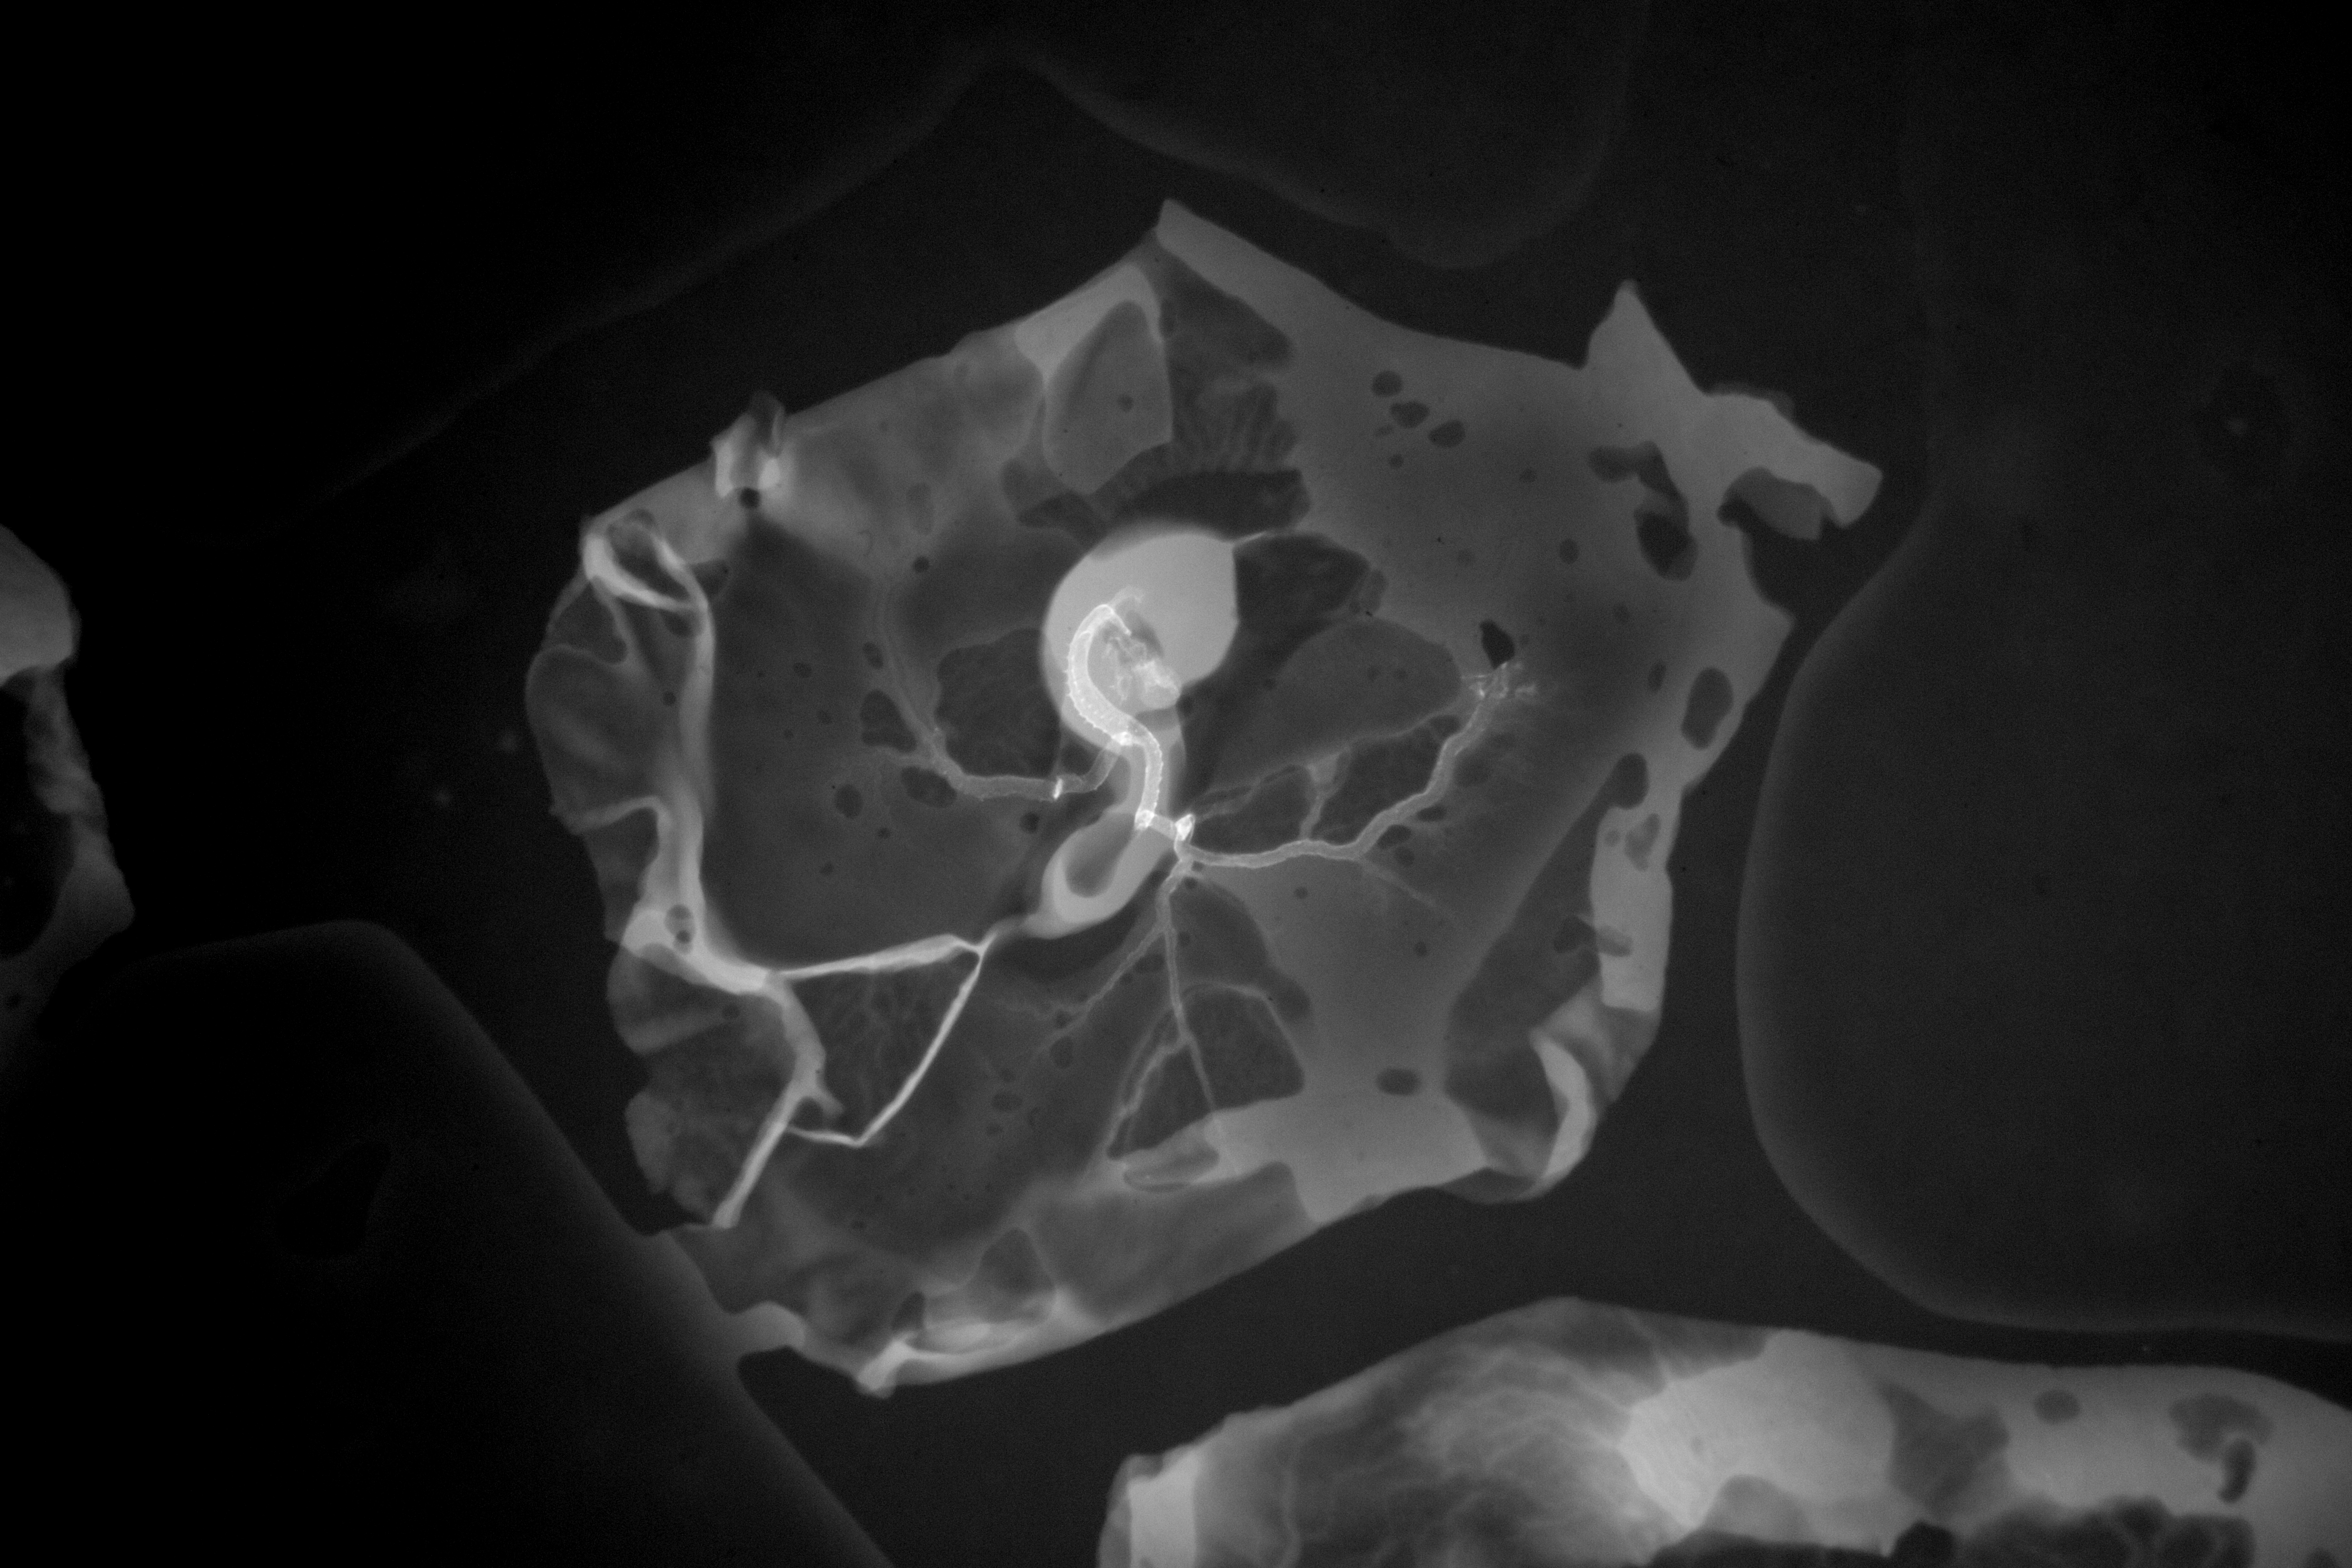

Chick Embryo Microangiography

Hamburger-Hamilton (HH) Stage 16 (approx. 2.1 - 2.5 days)

X-Ray Micrographs